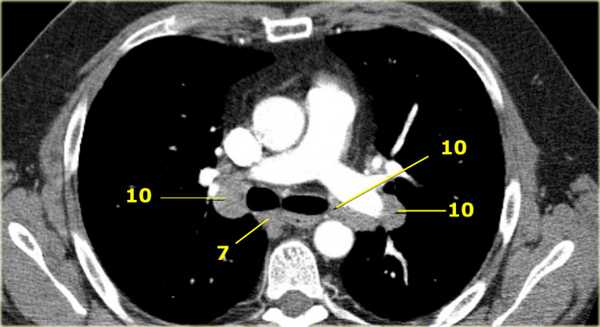

4L. Левые нижние паратрахеальные лимфатические узлы

4L узлы расположенные слева от левой стенки трахеи, между горизонтальными линиями проведенными касательно верхней стенке дуги аорты и линией проходящей через левый главный бронх на уровне верхнего края верхнедолевого бронха. Они включают паратрахеальные узлы расположенные кнутри от артериальной связки.

Узлы 5 группы (аортопульмонального окна) расположены кнаружи от артериальной связки.

На левом изображении над уровнем легочного ствола представлены нижние паратрахеальные узлы слева и справа, так же здесь представлены узлы 3 и 5 групп.

Изображение слева выше уровня карины. Слева от трахеи 4L узлы. Обратите внимание что они расположены между легочным стволом и аортой, но не в аортопульмональном окне, потому что они лежат медиальнее артериальной связки. Лимфатические узлы латеральнее легочного ствола относятся к 5 группе.

10. лимфатические узлы корня легкого

Лимфатические узлы корня расположены проксимальнее долевых узлов, но дистальнее медиастинальной дупликатуры и узлов промежуточного бронха справа.

Все лимфатические узлы 10-14 групп являются N1 узлами, так как они находятся вне средостения.